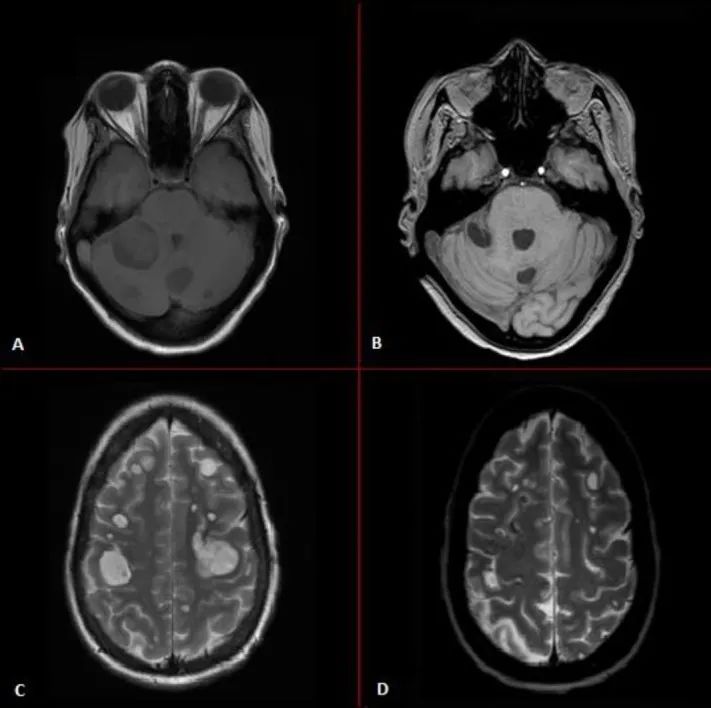

下面是M女士的MRI,A,C图显示在克唑替尼使用期间发生了多个颅内转移,B,D显示M女士接受劳拉替尼治疗一周后,颅内转移灶迅速消退,肿瘤标记物迅速下降。